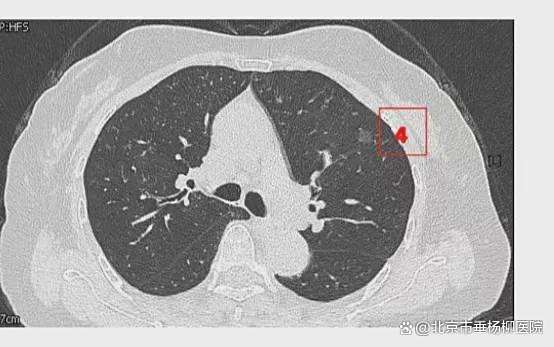

患者女性,71岁,因“发现左肺多发结节2周”入院。胸部CT提示左肺多发磨玻璃结节,较大者位于左肺上叶,呈类圆形,边界清晰,最大直径约9mm。该CT表现高度提示恶性可能。鉴于患者结节数量较多,为减少术中肺组织损伤,术前于CT引导下行经皮肺结节定位术,继而实施胸腔镜下左肺楔形切除术。术中共切除肺部结节6枚。术后病理示:左肺上叶较大结节(4号)为微浸润腺癌,其余5枚结节均为原位癌。患者术后恢复良好,于术后第1天拔除胸腔引流管,第4天顺利出院。

影像资料